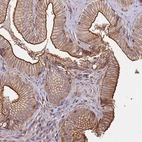

Immunohistochemical staining of human gallbladder shows strong membranous positivity in glandular cells.